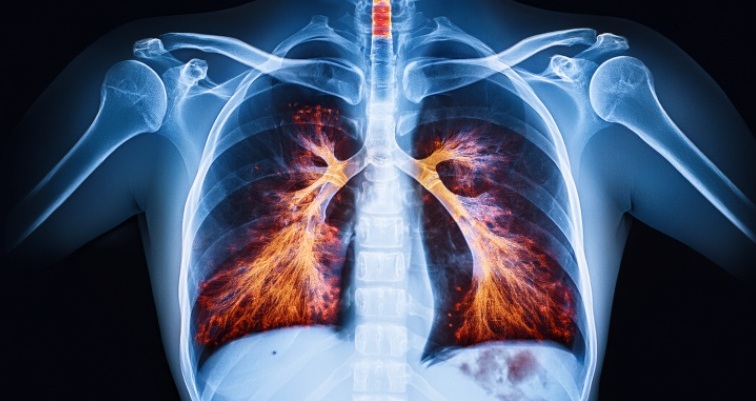

O diagnóstico da pneumonia é baseado na combinação de achados clínicos, laboratoriais e radiológicos. A radiografia de tórax é o exame de imagem mais utilizado, podendo revelar opacidades ou consolidações pulmonares características.